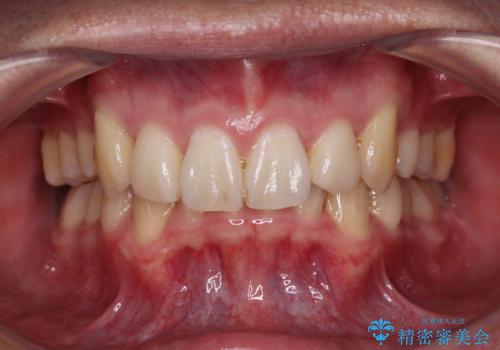

- 食いしばりが気になっていたとのことで来院された患者様です。

当初は睡眠時のマウスピースのみの製作をご希望でしたが、矯正治療の提案をしたところ、インビザラインにて矯正治療を行うこととなりました。

咬合力の緩和と食いしばりがちな咬み合わせが改善され、顎の負担が大幅に軽減されました。